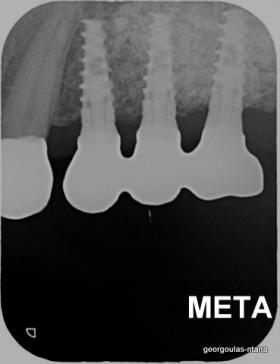

Στην ασθενή αυτή πραγματοποιήθηκε ανοικτή ανύψωση ιγμορείου άνω αριστερά. Σε πρώτη φάση πραγματοποιήθηκε η οστική αύξηση και 6 μήνες μετά τοποθετήθηκαν 3 εμφυτεύματα. Τόσο στην πανοραμική όσο και στην τομογραφία κωνικής δέσμης (CBCT) που πραγματοποιήθηκαν 6 μήνες μετά την ανύψωση είναι εμφανής ο σχηματισμός οστού. Η τελευταία ακτινογραφία και φωτογραφία λήφθηκαν 5 χρόνια μετά την προσθετική αποκατάσταση.